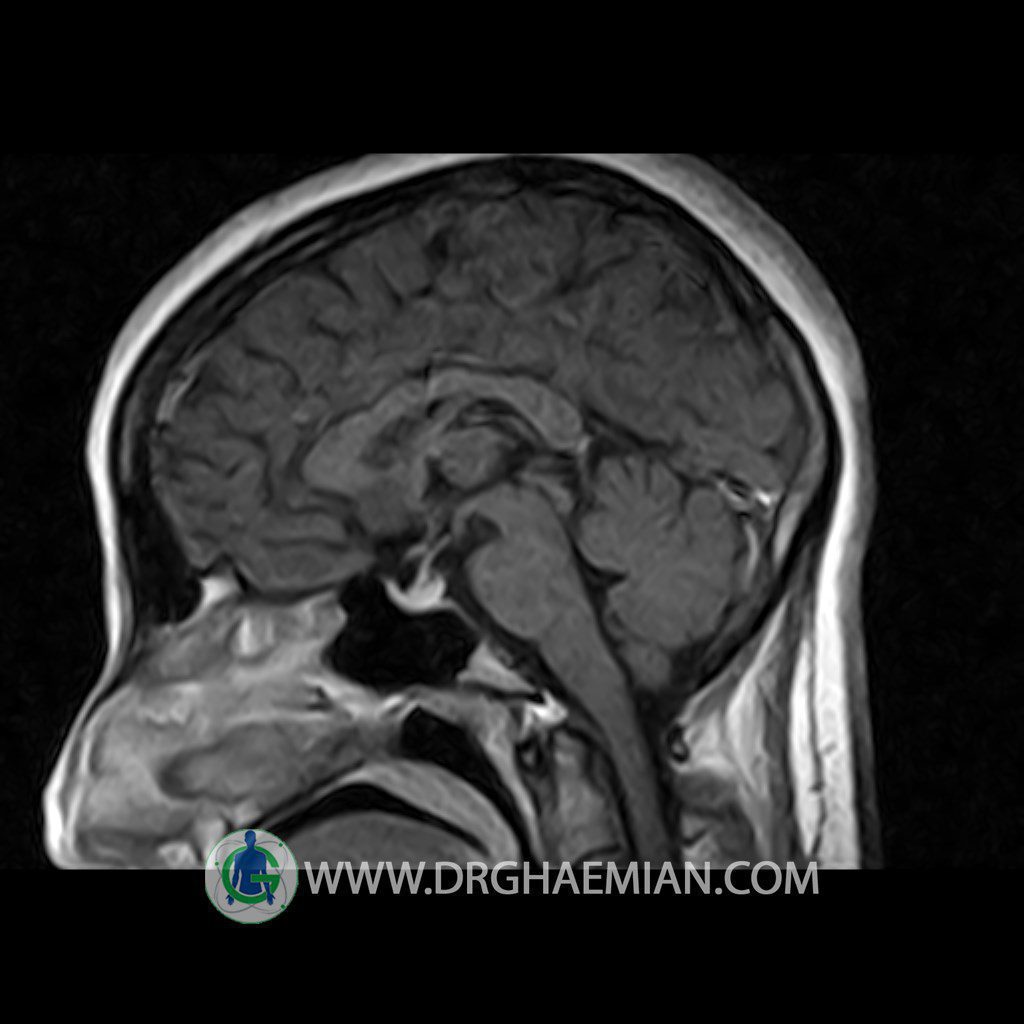

ام آر آی هیپوفیز یک روش تصویر برداری است که از غده هیپوفیز (غده ایی کوچک در مغز که هرومون ها و دیگر غدد بدن را کنترل می کند) و ناحیه های پیرامونش در مغز تصاویری ایجاد می کند. در این کیس سلای نسبتا خالی در ناحیه هیپوفیز بیمار مشاهده می شود.

HYPOPHYSIS MRI

(with and without contrast)

Technique: Axial , coronal T1 , Axial , coronal , sagittal T2 , Axial, coronal T1 post Gd & 64 dynamic thin coronal slices.

REPORT :

The pituitary tissue shows normal , position, shape , size and homogeneous signal intensity both before and after contrast administration .

Anterior and posterior pituitary gland were normal .

It contains no circumscribed hypointense or hyperintense areas .

The infundibulum is centered and of normal size .

The optic chiasm and suprasellar spaces appear normal .

The cavernous sinus and imaged portions of the internal carotid artery and carotid siphon are unremarkable .

Evaluable portions of the neurocranium show no abnormalities .

The sphenoid sinus is clear and pneumatized .

Imaging of the hypothalamus after contrast medium administration was normal.

– Extension of suprasella cistern to sella with thin pituitary gland in floor of sella ( partial empty sella )

is seen